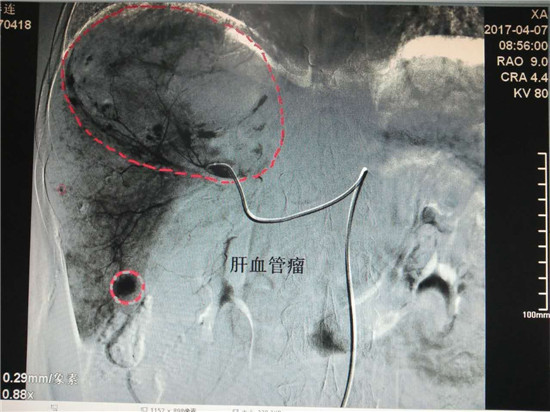

患者孙某,女性,62岁,在我院体检时发现患有巨大肝血管瘤(130mm×88mm),4月7日,在乐鱼手机站入口介入科行介入微创手术治疗。术前,科主任李建国详细分析评估了病情,组织科室人员制定了严密的手术方案,术中精细操作,在全体医护人员的密切配合下,历时40分钟,成功对患者肝脏巨大血管瘤实施了肝动脉超选择介入栓塞术。治疗过程患者处于清醒状态,无痛苦,术毕生命体征正常,安返病房。

肝血管瘤患者通常是在体检时发现,药物治疗几乎无效,传统的方法是外科手术,但因手术风险大,术后恢复时间长,对身体创伤比较大,成为了患有肝血管瘤患者的最大心病。近年来,肝血管瘤的微创治疗发展非常迅速,具有代表性的肝血管瘤介入治疗逐渐得到推广应用,在我院介入科已经熟练开展,为渭南及周边区域诸多患者带来了福音。